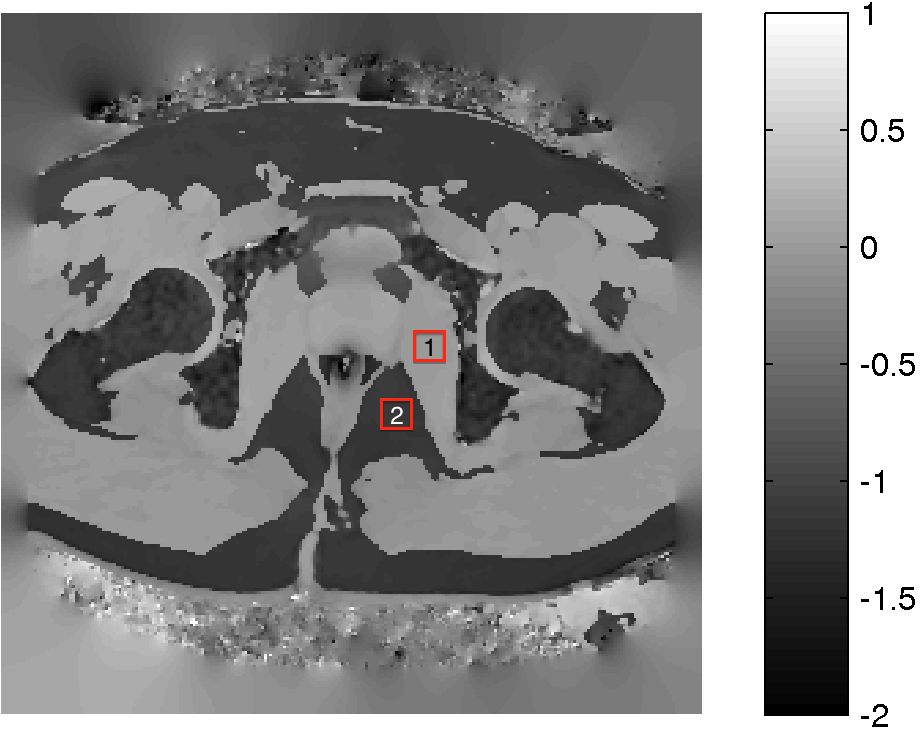

Figure 6: Background suppression of a ppm map with water and fat signal. (a): Magnitude of the first echo of a multi echo sequence. (b): PRF map estimation using ARMA technique.(c): Background suppressed PRF map. (d): Estimated background field map in ppm. The fat and water peak is aliased with 4.324.324.32 ppm due to the chosen echo spacing. the fat-water boundary. The labels 1 and 2 are water and fat ROIs that are used to determine the CNR gain of the method.

In this section we add Gaussian noise of various levels to a chemical shift image with high contrast to noise ratio (CNR) to test the robustness under noise.

An MFGRE sequence was used to collect using a 3T scanner (SIGNA; GE Healthcare Technologies, Waukesha, WI) 16 echoes with echo spacing of 1.816ms1.816𝑚𝑠1.816ms, TR=75ms𝑇𝑅75𝑚𝑠TR=75ms, Matrix 128×128128128128\times 128 and Pixel Bandwidth of 651.016Hz651.016𝐻𝑧651.016Hz. Figure 6 (a) illustrates the magnitude of the first echo of a slice through the pelvis. The multi echo data is processed pixel wise by the ARMA technique. The resulting PRF in ppm at each pixel is illustrated in Panel (b). The dark areas in panel (b) are subcutaneous lipid. Inhomogeneities of the PRF can be seen near the air inclusion in the middle and throughout the image, in particular in the lipid regions. The result of the background suppression technique is shown in Panel (c), which illustrates, that most of the background inhomogeneities have been removed. Note the fat-water ppm difference is about 1.16ppm1.16𝑝𝑝𝑚1.16ppm and not the expected shift of about 33.5ppm33.5𝑝𝑝𝑚3-3.5ppm. This is a consequence of aliasing introduced by the finite sampling in echo direction. If the aliasing is taken into account by adding the bandwidth of 4.3212ppm4.3212𝑝𝑝𝑚4.3212ppm, then the fat-water shift is 3ppm3𝑝𝑝𝑚3ppm as expected. The pixel wise difference of the images in Panels (b) and (c) is shown in Panel (d). Note that the estimated background field 𝚽𝐛subscript𝚽𝐛{\bf\Phi_{b}} is smooth in areas of transitions of fat and water. The map is not necessarily smooth in areas of low signal, however a correct estimation of the background in low signal areas is not a well-posed problem.

Noise is added to the original ppm map and a contrast to noise ratio is computed as follows: Two regions of interest (ROIs) are selected Rw,Rfsubscript𝑅𝑤subscript𝑅𝑓R_{w},R_{f}, one in water the other in fat, labeled 1 and 2 in Figure 6 (c). The size of the ROI is 11×11111111\times 11 pixels. The CNR is computed as

CNR=mean(Rw)mean(Rf)std(RwRf).𝐶𝑁𝑅meansubscript𝑅𝑤meansubscript𝑅𝑓stdsubscript𝑅𝑤subscript𝑅𝑓CNR=\frac{\textrm{mean}(R_{w})-\textrm{mean}(R_{f})}{\textrm{std}(R_{w}\bigcup R_{f})}.